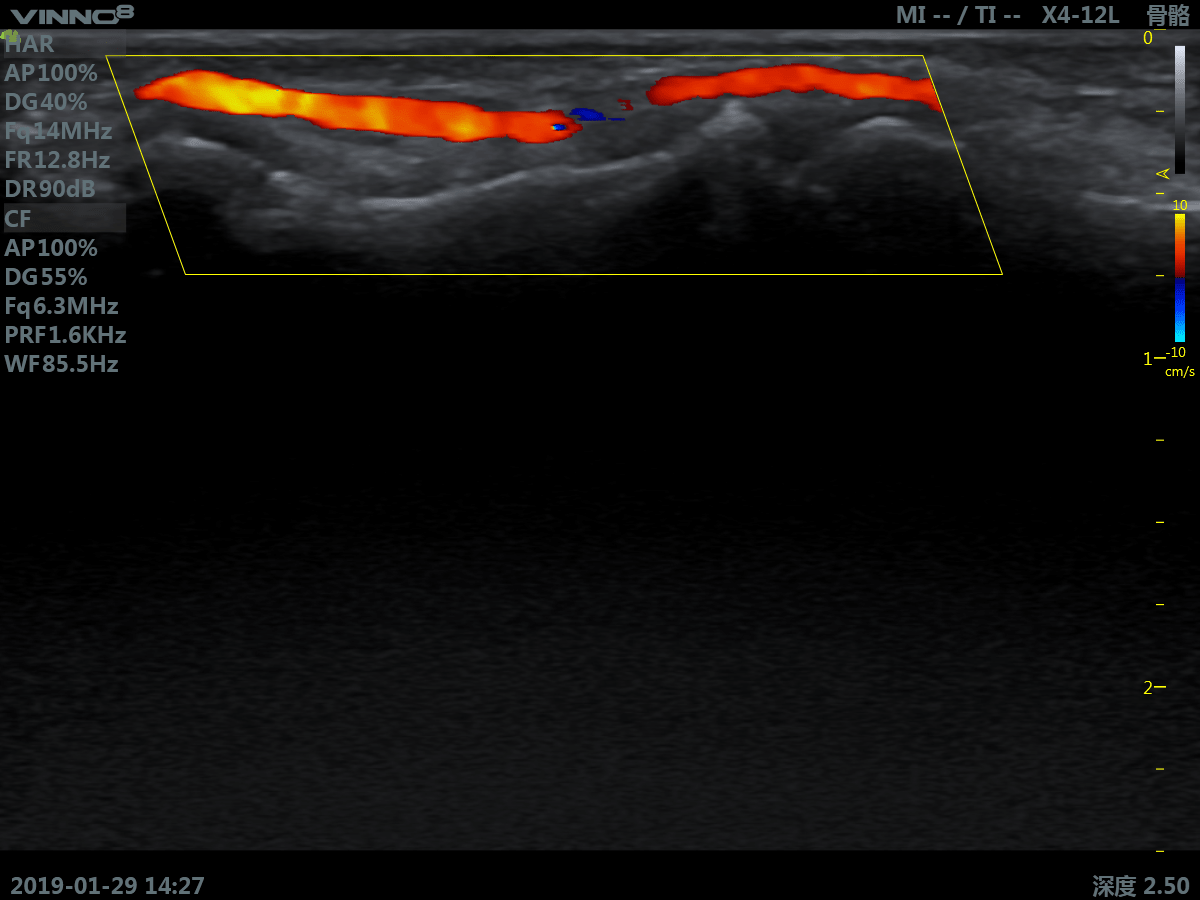

- периферические сосуды

10. CFM. Режим цветового допплера

11. CFM+B (B+CF). Комбинированный режим: цветовое допплеровское картирование + В режим

12. PDI. Режим энергетического допплера.